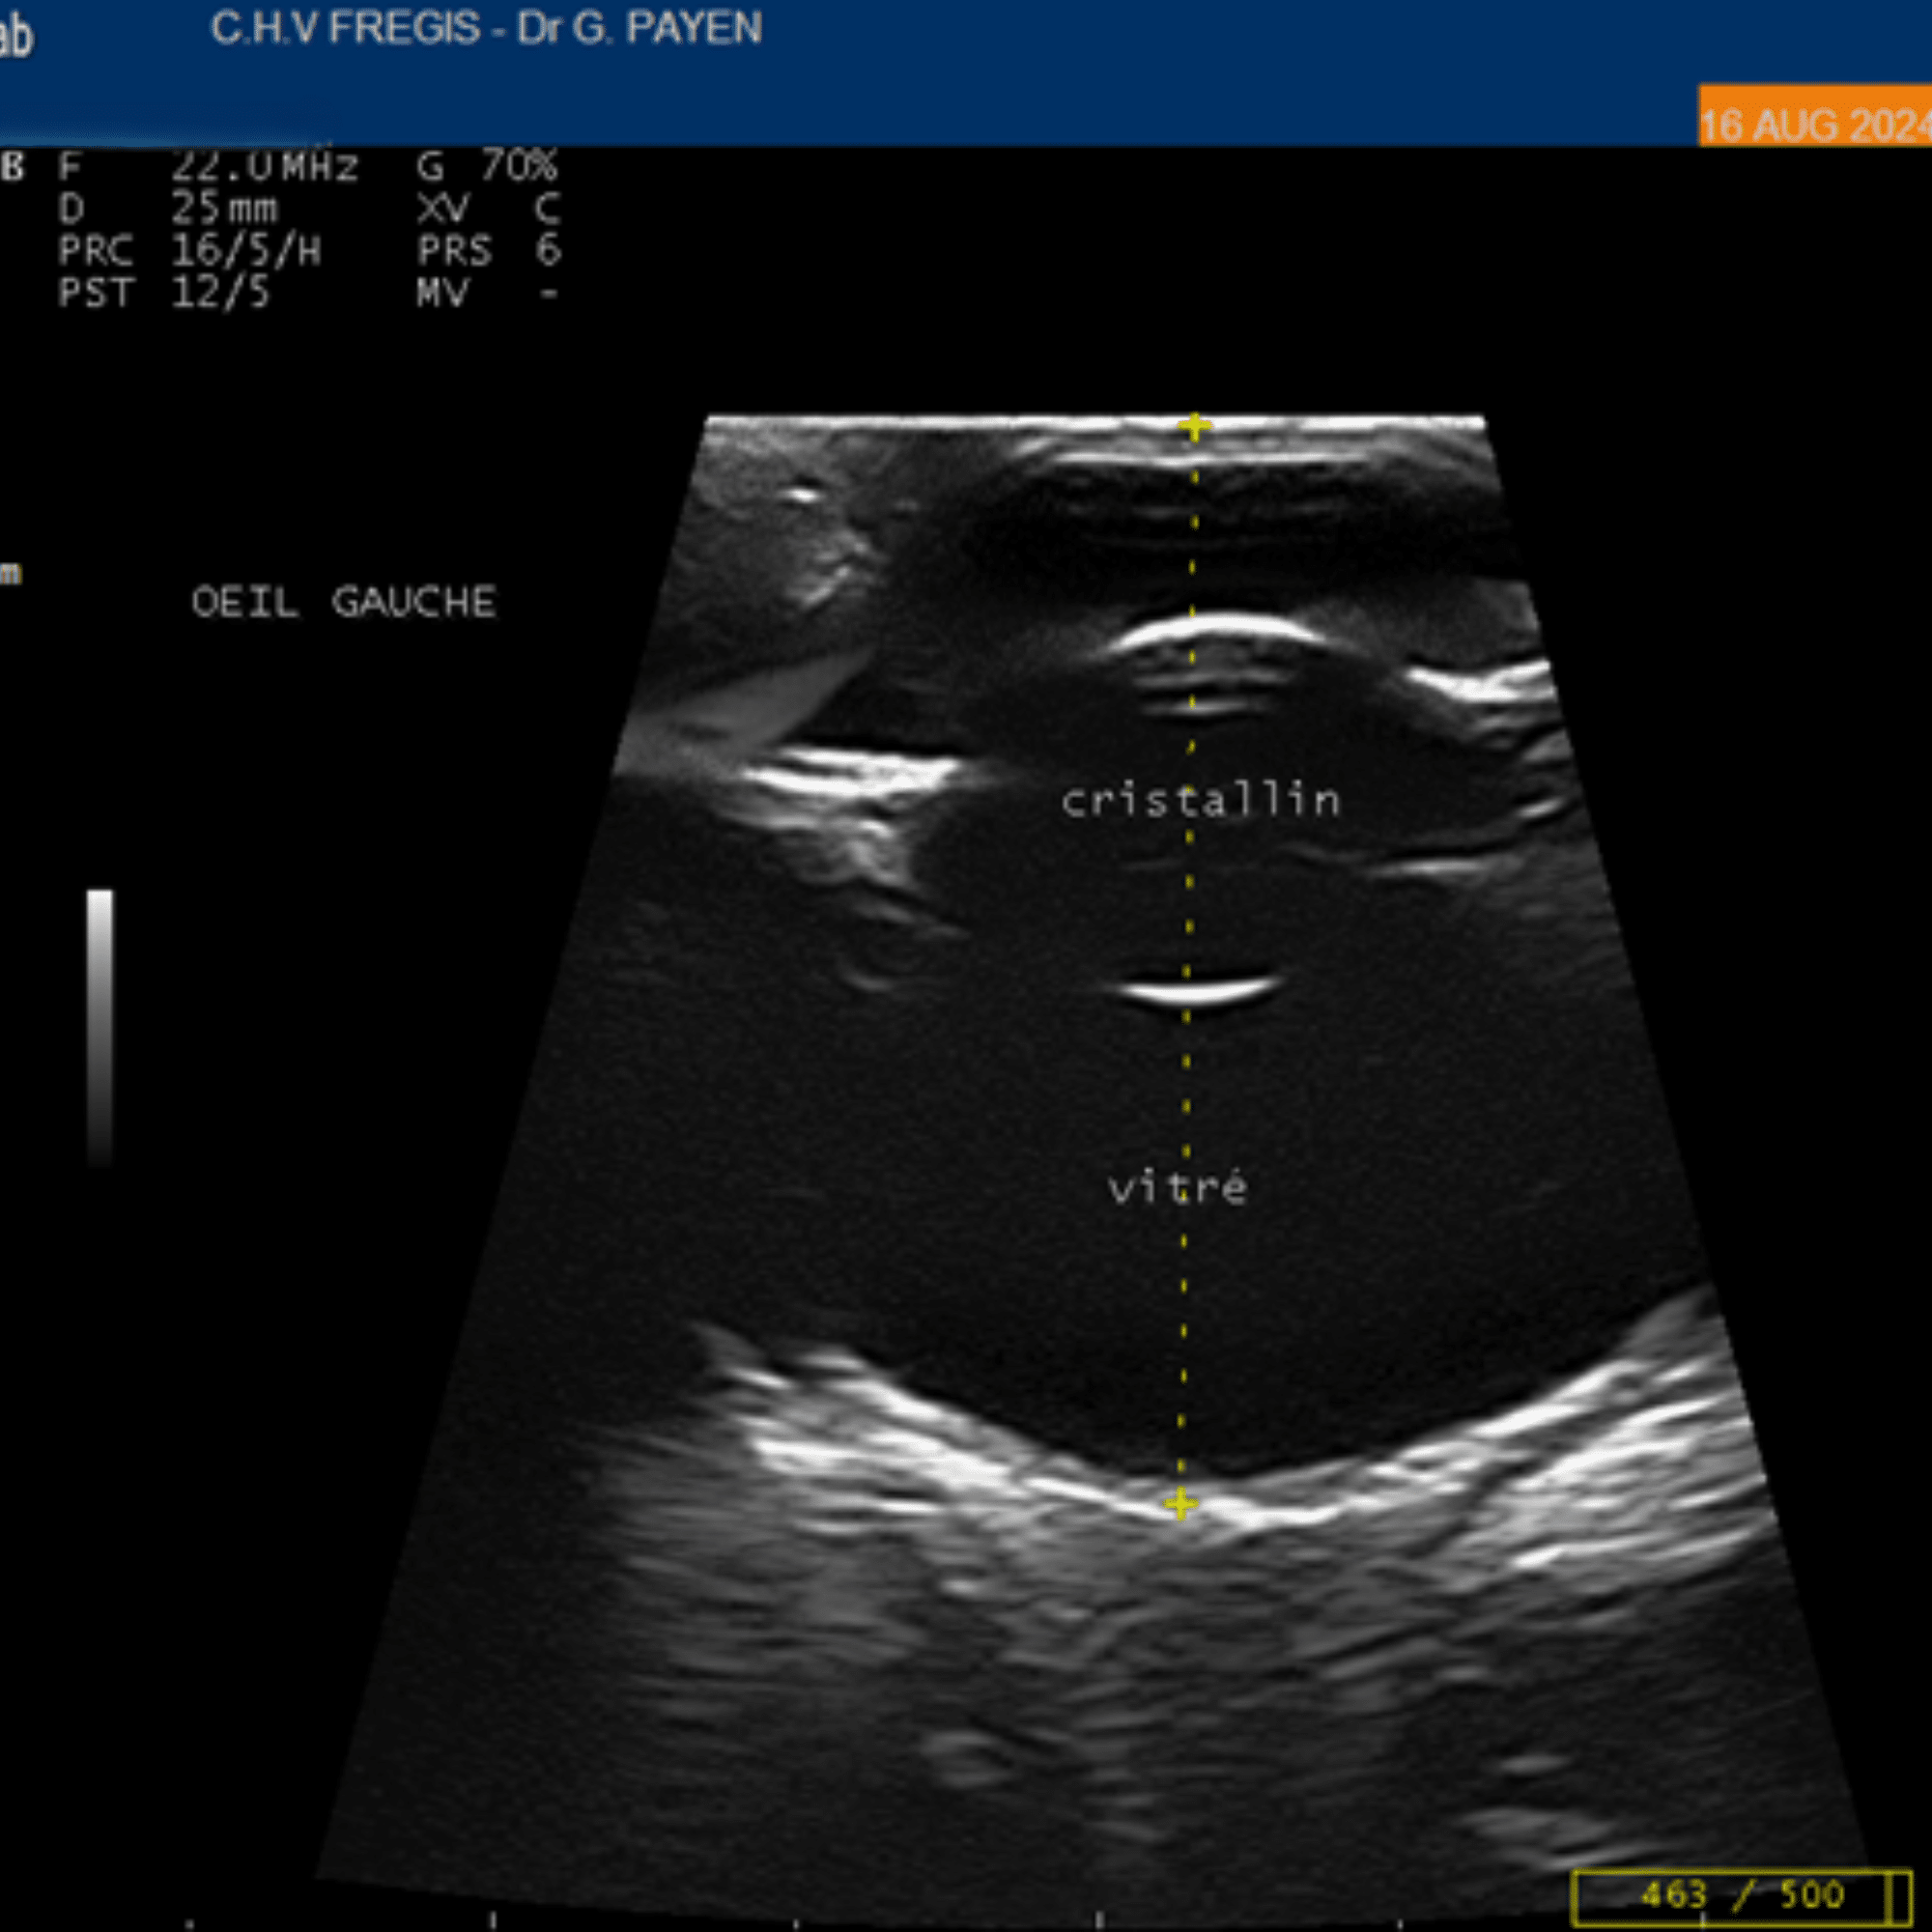

L’échographie oculaire

Celle-ci est effectuée en consultation sous simple anesthésie locale grâce à un appareil dédié à l’ophtalmologie vétérinaire. Cet examen est indiqué lorsque des opacités (de la cornée, de la chambre antérieure de l’œil ou du cristallin) empêchent l’évaluation de certaines structures de l’œil. Cet examen est très utile pour établir un pronostic visuel après des traumatismes de l’œil (griffure de chat ou contusion du globe oculaire). L’examen permet aussi dans certains cas de diagnostiquer une luxation du cristallin, un décollement de rétine, une hémorragie ou encore une tumeur intraoculaire.